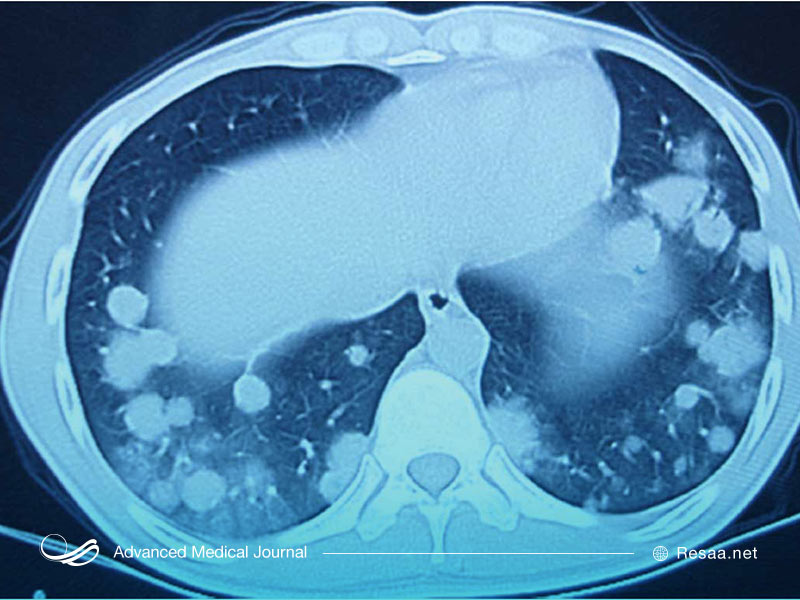

آزمایشات تصویربرداری به منظور تشخیص گرانولوماتوز

این آزمایشات از بدن شما عکس میگیرد تا به دنبال آن، آسیب اعضای بدن بررسی شود:

- اشعه ایکس. در اشعه ایکس قفسه سینه، از اشعه کمی برای گرفتن عکس از منطقه آسیبدیده مانند ریهها و رگهای خونی استفاده میشود.

- سی تی اسکن. در این آزمایش از رایانهها و دستگاههای اشعه ایکس چرخان به منظور گرفتن عکسهای دقیقتر از منطقه آسیبدیده استفاده میشود.

- اسکن امآرآی. MRI با استفاده از آهنربا و امواج رادیویی تصاویر دقیق و مقطعی از منطقه مورد نظر را تولید میکند، بدون اینکه استخوانها مانع از دیدن بافتها و اندامها شوند.